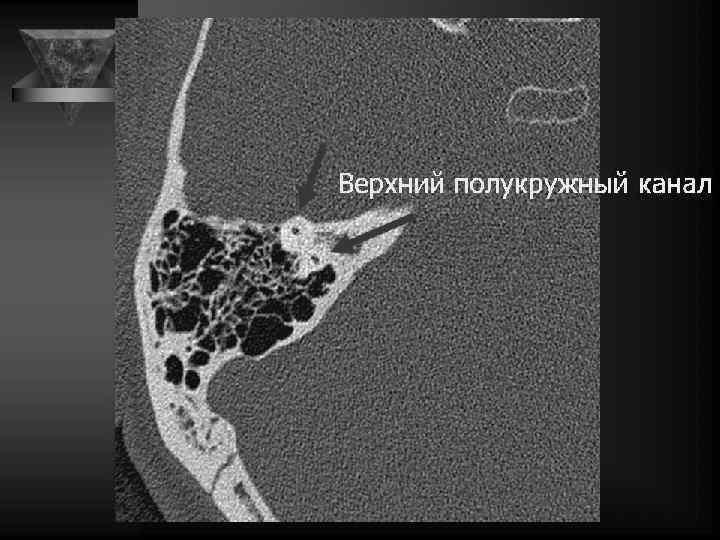

Внутреннее ухо и верхушка пирамиды • Улитка: деминерал-я костной капсулы, спирал-й канал улитки и его просвет, оссификация • Преддверие и полукружные каналы, интактные стенки, оссификация • Внутр. слух. проход: расширение, неровн-ть контура, деструкция кости, стеноз • Канал лицев. нерва до коленч. ганглия. • Водопровод преддв-я и водопр. улитки. • Верхушка пирамиды: губчатая или пневматизирована, наличие секрета, наличие образований